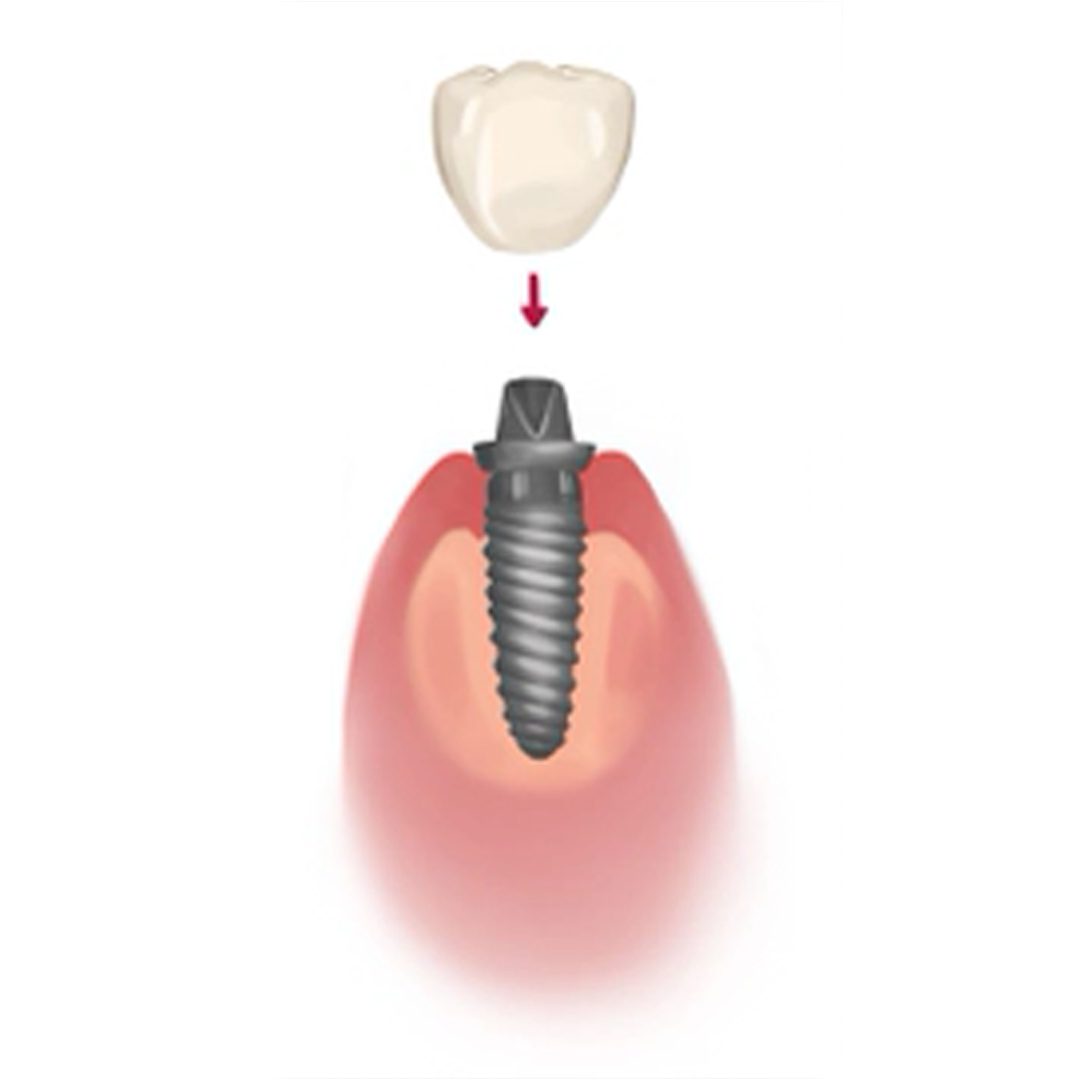

Core Stages of Implant Surgery

The entire dental implanting process can generally be broken down into four core stages, spanning over the course of 4 – 6 months in total. The four stages are; implant fixture placement, healing & osseointegration, abutment placement and the placement of the final dental prosthesis.

Once the dental implant fixture has adequately osseointegrated with the jaw bone, the abutment and prosthesis can be attached to the implant fixture, completing the entire dental implant process.

4. Prosthesis Placement

The final prosthesis is permanently cemented to the abutment.

5. Prosthesis Placement

After the dental implant fixture has successfully integrated with your jaw bone, a fully customised dental prosthesis will be made to meet your needs and requirements, such as an implant crown, implant supported bridge, implant retained denture or All-on-4 denture.

The dental prosthesis will be designed to blend naturally with your other teeth and fit perfectly inside your mouth.

While the permanent prosthesis is being manufactured in a dental lab, you’ll be fitted with a set of temporary prosthesis (crown, bridge or denture) to use.

Once completed, the permanent prosthesis will be fixed onto your dental implants, giving you a brand new and improved smile to show the world.

5. Prosthesis Placement

After the dental implant fixture has successfully integrated with your jaw bone, a fully customised dental prosthesis will be made to meet your needs and requirements, such as an implant crown, implant-supported bridge, implant-retained denture or All-on-4 denture.

The dental prosthesis will be designed to blend naturally with your other teeth and fit perfectly inside your mouth.

While the permanent prosthesis is being manufactured in a dental lab, you’ll be fitted with a set of the temporary prosthesis (crown, bridge or denture) to use.

Once completed, the permanent prosthesis will be fixed onto your dental implants, giving you the finished product and a brand new smile to show the world.